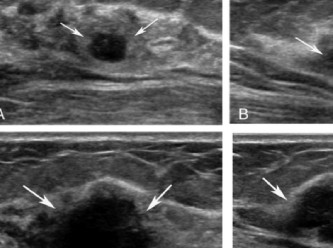

Tıp bölümünü seçerek belki de hayatını kurtaran Sally Rohan adlı öğrenci papiller tiroid kanseri olduğunu ultrasonografi makinesi kullanımı dersi sırasında öğrendi

Tıp bölümünü seçerek belki de hayatını kurtaran Sally Rohan adlı öğrenci papiller tiroid kanseri olduğunu ultrasonografi kullanımı dersi sırasında öğrendiğini söyledi.

Geçen sene ders sırasında makinenin nasıl kullanıldığını öğrenmek için tiroidinin kontrol edilmesini kabul eden 27 yaşındaki öğrenci, "Good Morning America"ya verdiği röportajda "Bize tiroidin ultrason ile görülebileceği öğretildi. Dersten önce izlediğimiz videolarda gördüklerimizle benim vişeomu karşılaştırıyorduk ve ona bakıp 'Durun, benimkinde bir sorun var. Benimki inişli çıkışlı görünüyor' dedim.

New Jersey'de okula devam eden Rohan, profesörünün tiroidindeki şişliğin bir nodül olduğunu, ultrason fotoğrafı ile birlikte bir doktora görünmesini istediğini söyledi.

Her ne kadar ilk kan testlerinde herhangi bir komplikasyon görülmese de yaklaşık bir sene sonra yapılan ikinci ultrasonda sonuçlar tiroid kanserinin en yaygını olarak bilinen papiller tiroidin birinci evresini işaret etti.